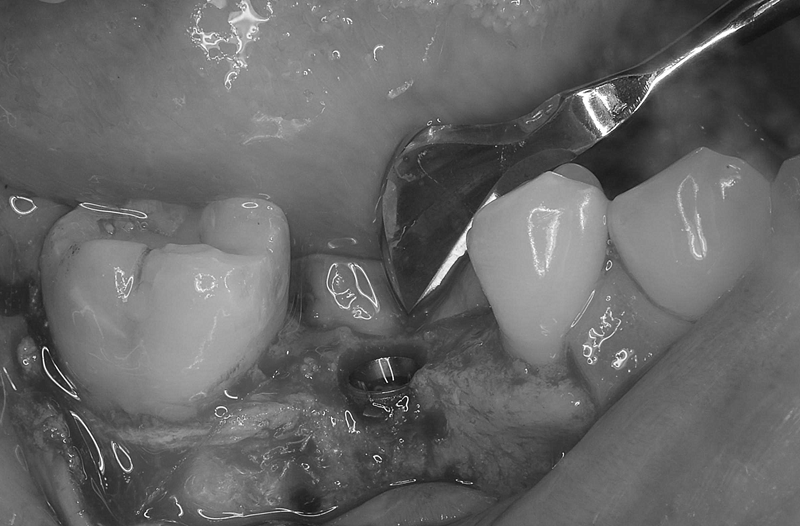

Case7

術前

術中

術後

| 治療名 | 抜歯即時インプラントとソケットリフトによる上顎臼歯部の修復症例 |

|---|---|

| 治療説明 |

歯の根が破折していたため抜歯が必要となり、患者さんとご相談のうえ、インプラントによる治療を選択しました。 ただし、インプラントを支える骨の高さが不足していたため、**上顎洞に骨を足す“ソケットリフト”**を併用し、安全にインプラントを埋入しました。 |

| 治療回数・期間 | 約3ヶ月 |

| 副作用とリスク |

・入れ歯や従来のブリッジと比べて、治療期間が長くなる傾向があります。 |

| 料金(税込) | 小規模GBR:110,000円 ソケットリフト:165,000円 インプラント一次手術:220,000円 二次手術:55,000円 上部構造〈セラミック〉:165,000円 合計:715,000円 |